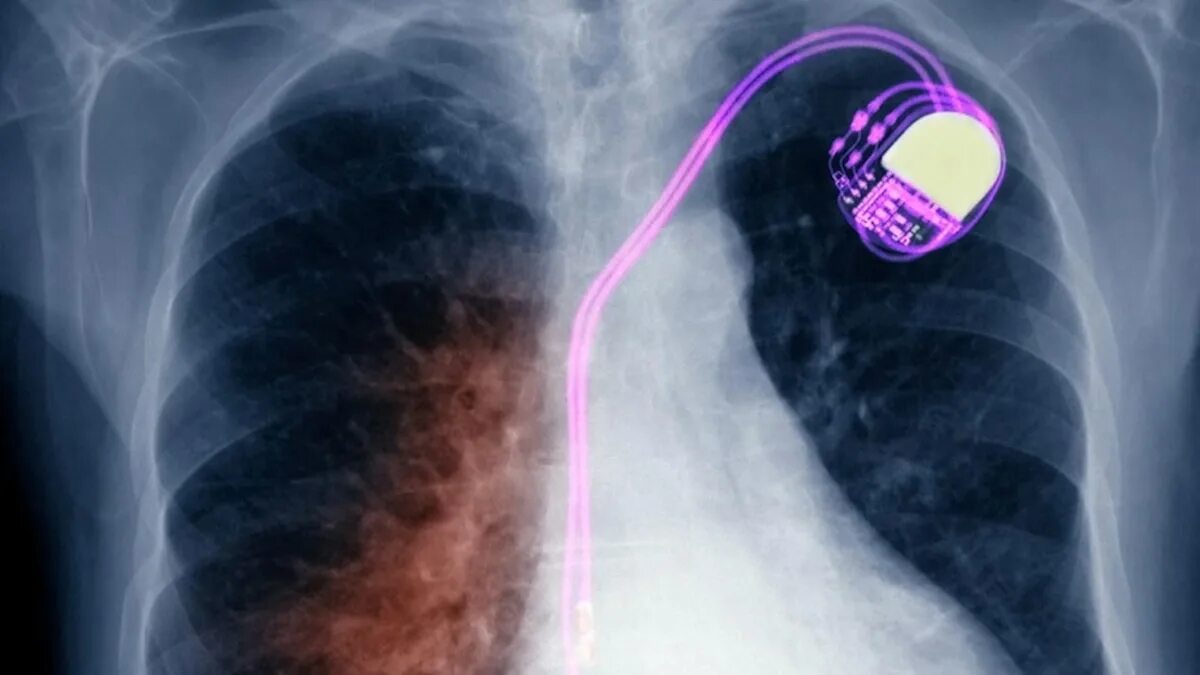

Почему в легких